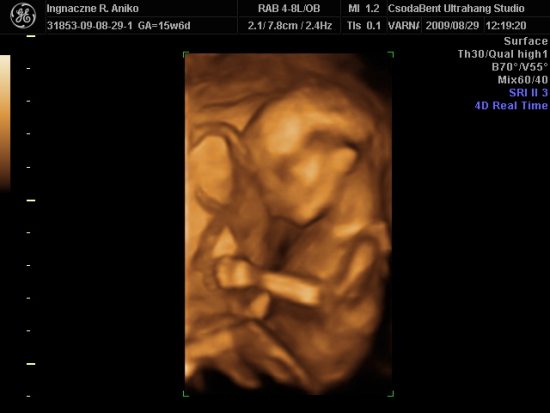

Lois is jelen